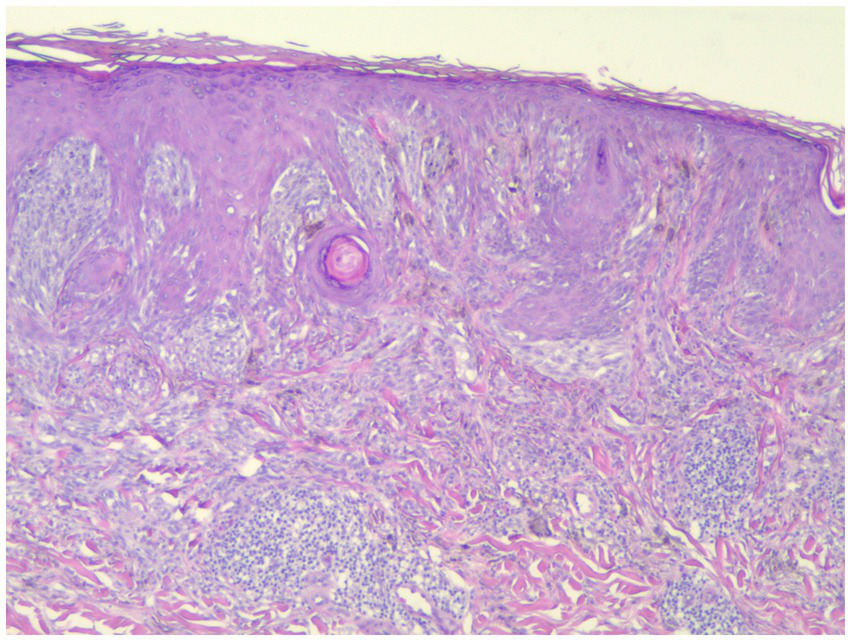

Figure 1

This spitzoid melanoma failed to stain with PRAME but was positive by FISH (H&E; 40×).